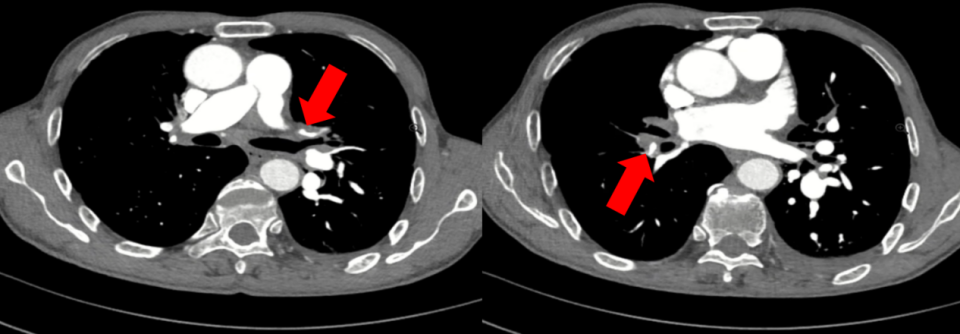

我们充分回顾了患者的个人史和外院胸腔积液引流后的CT,发现患者左下叶肺血管的许多分支都出现了比较明显的扩张。如果患者存在一侧肺静脉的狭窄或者闭塞,导致肺循环回流受阻,从而出现静水压升高,则可以解释他的单侧漏出液。我们与放射科的专家们讨论后,给患者完善了左房CTA观察患者的肺静脉情况。

通过左房CTA,我们的确发现患者的两个肺血管异常:1、左上肺静脉、右肺静脉中支未显影,提示存在局部静脉闭塞或缺如(图3a箭头所示);2、左下肺动脉多个分支扩张(图3b箭头所示)。

为了进一步明确肺动脉和肺静脉异常的表现,我们随即给患者检查了肺动脉CTA。我们发现除了上述肺血管异常,左上叶前段及尖后段动脉开口处狭窄,右上叶动脉开口狭窄,右叶间动脉明显缩窄,右肺中叶及下叶内前外段动脉闭塞(图4箭头所示)。

图3a:左房CTA提示左上肺静脉未显影

图3b:左房CTA提示左下肺动脉分支扩张

图4:肺动脉CTA提示左上叶前段及尖后段动脉开口处狭窄、右叶间动脉明显缩窄